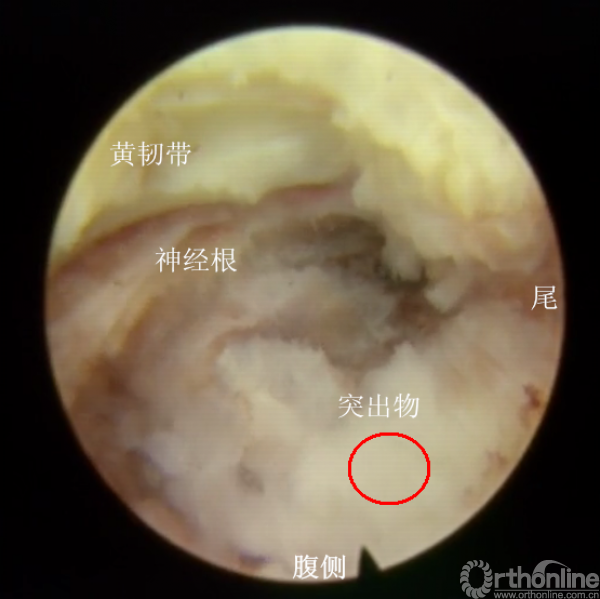

镜下显示置管正中靶点,但上关节突部分残留,予以镜下再次成型

镜下成型后,已经能够看到突出物的尾端

拖拽尾端,仅取出部分,且见突出物卡压明显

取出部分尾端后,仍有残留,且神经根卡压

咬除部分黄韧带,再次减压后见结构清晰

满屏的脱出一块髓核

但见神经根远端波动仍然不明显,且尾侧见有卡压物

工作套管往尾端移后,见一突出物,且相应节段的神经根波动差

逐步减压后,取出突出物后,见整个走行的神经根波动明显